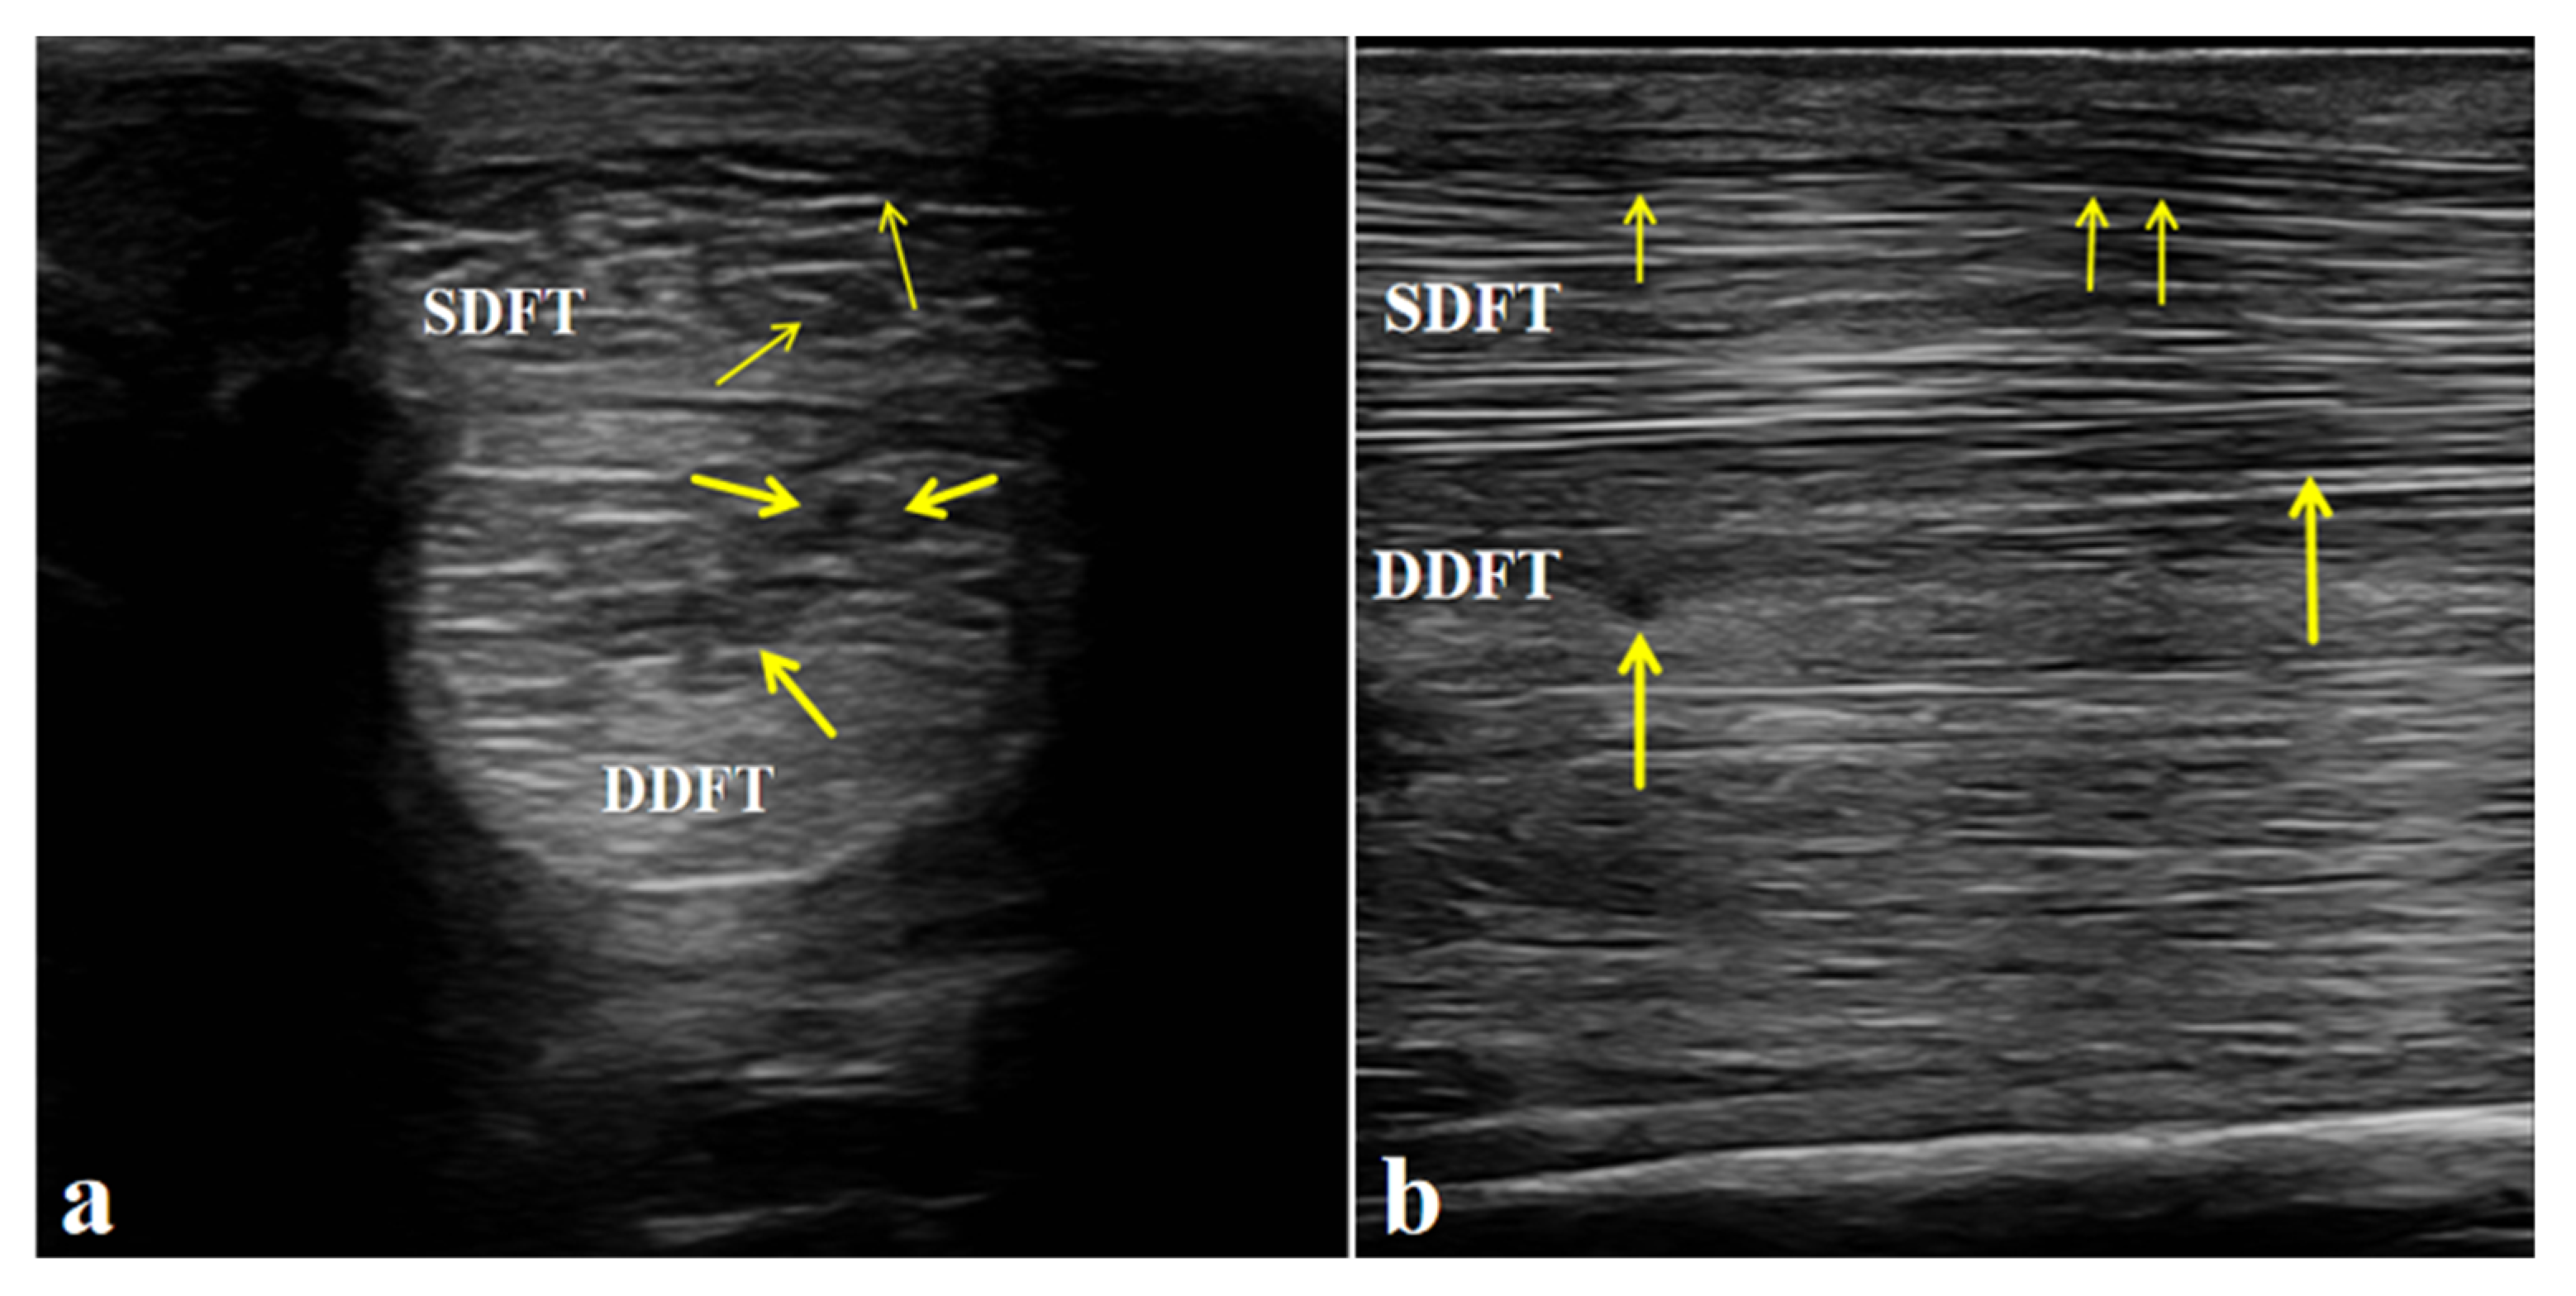

Ultrasonographic examination of the affected limb (left forelimb) showed a marked increase in the cross-sectional area of both the superficial digital flexor tendon (SDFT) and the deep digital flexor tendon (DDFT) compared with the contralateral side. The tendon margins were still visible, although slightly roughened. The normal parallel fibrillar echogenic pattern was almost completely lost and replaced by a diffuse, heterogeneous, mildly hypoechoic appearance. These findings indicate mild injury to both the SDFT and DDFT and are consistent with the diagnosis of flexor tendinitis (Figure 3).

Figure 3. Ultrasonographic features of the affected horse with flexor tendinitis. (a) Transverse sonograms of the superficial digital flexor tendon (SDFT) and deep digital flexor tendon (DDFT) (yellow arrow: lesion sites). (b) Longitudinal sonograms of the SDFT and DDFT (yellow arrow: lesion sites). Arrows indicate the sites of tendon injury.